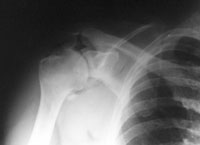

Ein 44-jähriger Patient ist auf dem ersten Eis des Winters ausgerutscht und auf die rechte Schulter gestürzt.

Er klagt über starke Schmerzen im Bereich der rechten Schulter und ein Instabilitätsgefühl im Gelenk. Die Beweglichkeit des Arms ist aufgrund der Schmerzen eingeschränkt, Durchlutung und Sensibilität sind normal.

linke Schulter tangential

Welche Befunde liegen vor (mehrere richtige Antworten möglich)?